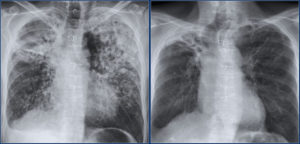

Бронхоэктазы в легких

Метастатические бронхоэктазы в легких представляют собой патологические расширения бронхов (обычно цилиндрической или мешковидной формы), спровоцированные деструктивным поражением бронхиальных стенок и окружающих тканей.

Бронхоэктазы после туберкулеза

Такие изменения обусловлены не только деформацией бронхов, но и повышенным внутрибронхиальным давлением из-за рубцового стеноза или сдавления дыхательных путей увеличенными лимфоузлами.

Бронхоэктазы увеличивают риск развития гнойного процесса и возникновения легочных кровотечений, поэтому требуют наблюдения и лечения, если процесс прогрессирует или приводит к выраженной дыхательной недостаточности.